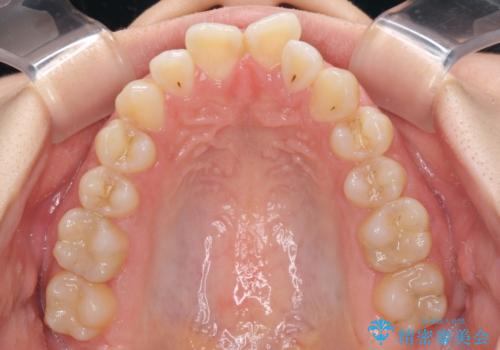

- 前歯の上下スペースによる食べにくさを気にして来院された患者様です。

インビザラインにより上下の前歯の隙間を閉じていくこととしました。

前歯のデコボコの解消と並行して上下の奥歯を圧下させるようにすることで、前歯を接触させるように計画しました。

上下の隙間に舌が入り込むことがオープンバイトの原因であったため、舌の筋肉のトレーニングも並行して行い、後戻りの抑制を図りました。